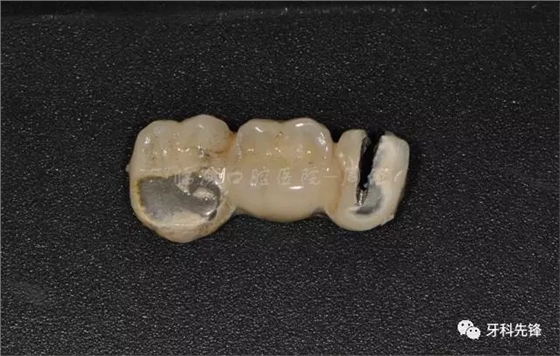

圖7原烤瓷冠修復(fù)體

640.webp (8).jpg